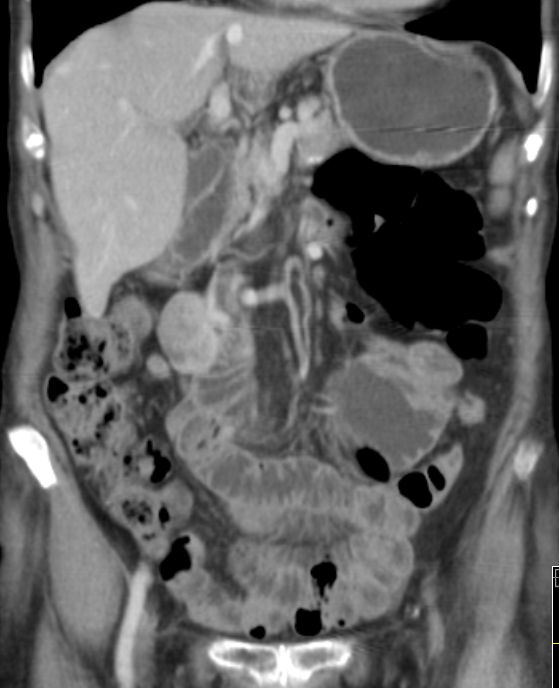

56-jähriger Mann mit großer Raumforderung der Magenvorderwand.

Gallenblase und Leber werden etwas verdrängend.

Vergrößerte Lymphknoten sind nicht nachweisbar.![]() | |||||||||||||||||||||||||||||||||||||||||